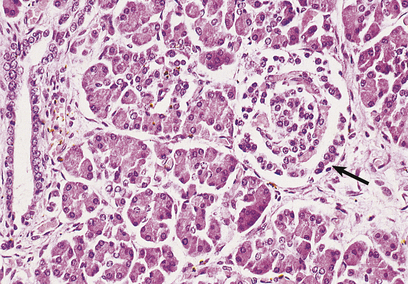

Phaeochromocytomas are brown, solid nodules, usually under 50 mm in diameter, often with areas of haemorrhagic necrosis (Fig. 17.9). Histologically, they consist of groups of polyhedral cells which give the chromaffin reaction, and are highly vascular (Fig. 17.10).

Fig. 17.10 Chromaffin cells in a phaeochromocytoma. There are groups of cells with granular cytoplasm, amidst which there are numerous branching capillaries.